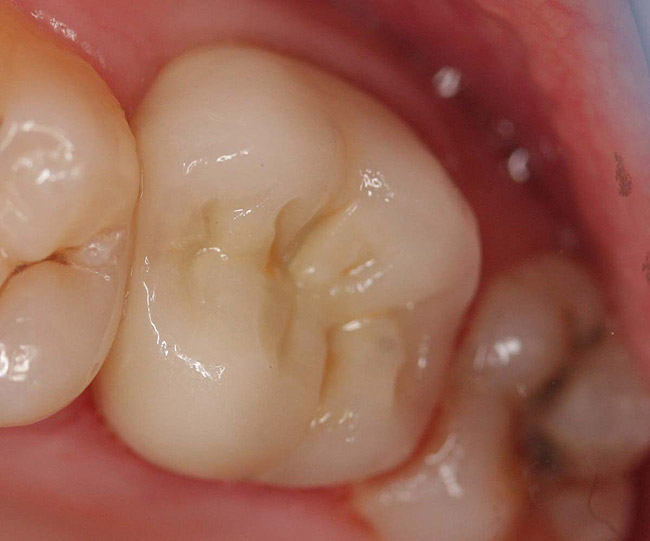

Case 1

A Class IN maxillary bicuspid was previously restored with a fiber post and an all-porcelain crown (Figure 1). The forces of the oral environment resulted in fracture of the fiber post and crown failure. The remaining fiber post in the root was removed, and anti-rotational areas were prepared for a cast post (Figure 2). A gold cast post was constructed at a dental laboratory, using an indirect technique (Figure 3). A porcelain-fused-to-metal (PFM) crown was constructed with a bevel finish to provide a ferrule and reduce forces on the post (Figure 4 and Figure 5).

Figure 1  X-ray of an endodontically treated second bicuspid restored with a fiber post, core, and all-porcelain crown.

Figure 1

Figure 2  Same second bicuspid as Figure 1 after removal of the fractured fiber post.

Figure 2